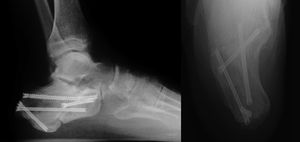

ResultsWe recorded 46 intraarticular fractures in 43 patients (three bilateral). Thirty five were male and eight were female, with a mean age of 42 years (18−79) and a mean follow-up of 57.39 months (33–129). In all cases preoperative CT was performed resulting in: 11 Sanders type II, 23 type III and 12 type IV cases (Table 2). With regard to surgical technique, a standard “L” shaped approach and osteosynthesis with low-profile blocking plates was used in 21 patients (12 Sanders type IV patients and 9 Sanders type III patients), in 10 cases a minimally invasive approach was used of the sinus tarsi (10 Sanders type III cases: four cases synthesized with cannulated screws and six cases with ad hoc anatomical plates with/without cannulated screws (Figs. 1 and 2) and in 15 cases we decided to use an indirect reduction and percutaneous fixation with cannulated screws (11 Sanders type II and four Sanders type III cases) (Fig. 3 ) (Table 2).

Postoperative CT (defined as that performed prior to hospital discharge of the patient or in the first month of follow-up) was performed only in those cases in which the surgeon considered that pain radiology would not clarify the quality of the joint reduction, resulting in a total of 17 cases (37% of the series, six Sanders type IV patients treated with the “L” approach, nine Sanders type III patients treated by sinus tarsi and two Sanders type II patients treated with closed reduction and fixation with screws). The reduction of the posterior subtalar joint measured by CT was satisfactory in 12 cases (defined as an articular displacement < 2 mm). In the other five cases the displacement was above 2 mm (one Sanders type iv case, one Sanders type iii case of tarsi sinus, one Sanders type iii case with indirect reduction and cannulated screws and two Sanders type ii cases also with indirect reduction). Reintervention was decided in only one case (patient with Sanders type II fracture) with an “L” approach and low-profile plate, with good radiological and functional outcome. Of the remaining four cases the risk/benefit balance of further surgery called for conservative treatment, particularly due to the further aggression to soft tissues. The average preoperative Böhler angle was 6.45 ± 10.21 ([-22]-25) and postoperative angle was 20.46 ± 7.09 (4−38). CT in follow-up (defined as over one year after surgery) was performed in 31 cases, only in those where three was suspicion of a post-traumatic degenerative pathology following analysis of plain radiology: subtalar osteoarthritis was diagnosed in 19 cases (symptomatic in 12, seven of them treated with subtalar arthrodesis) and calcaneo-cuboid osteoarthritis in six cases (only one symptomatic and treated conservatively) (Table 3). The AOFAS was 74.28 ± 18.98 (27−100) and the VAS 4.14 ± 2.98 (2–9).

Regarding surgery, the lateral “L” approach which was used as the gold standard is not exempt from complications, particularly of soft tissue, with percentages reaching up to 35% in some authors.22 As a result, during the last 10 years indirect, percutaneous techniques or those with minimal incision have been developed, which seek to minimize aggression of soft tissues, respecting joints. These have obtained similar or even superior clinical outcomes to open techniques.24–26 In our series we recorded 25 cases treated with minimally invasive techniques, with an average AOFAS score of 78.45 points. Although this was only recorded in 10 cases, the tarsi sinus approach has in the last 5 years become our technique of choice in most cases. In 2017 a randomised prospective study was published, comparing open surgery using the “L” technique with minimally invasive techniques, showing better radiological results in the minimally invasive technique, but not in functional results. Osteosynthesis techniques using percutaneous screws obtained the poorest results,27 although this was not visible in our series.